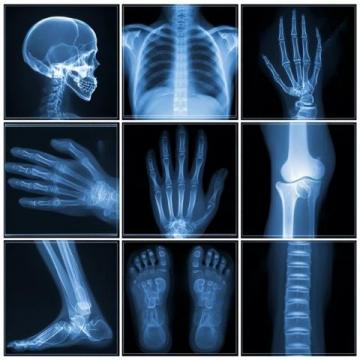

2. 必背口訣匯總:我們精心挑選了一系列覆蓋基礎(chǔ)解剖學(xué)、放射防護(hù)及物理學(xué)等核心領(lǐng)域的口訣。每個(gè)口訣都配有詳盡解析,幫助大家深入理解其背后的知識(shí)內(nèi)涵。